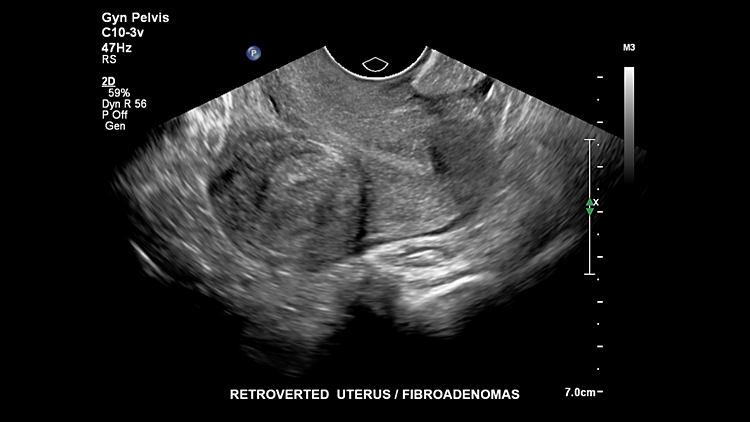

Ревервертированная матка, C10-3V

Фиброаденома матки, C10-3v

Фиброаденома матки, C10-3v